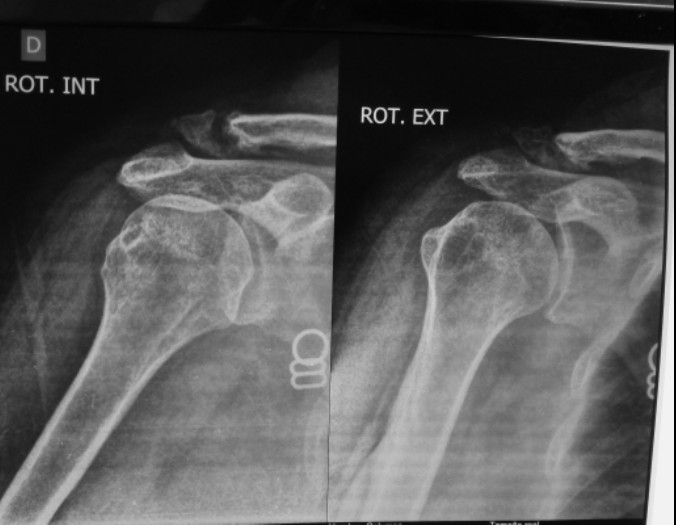

Господа коллеги, нужны ваши мнения. Имеется пациент женщина, возраст 45

лет. Перелом более двух лет назад. Год назад ей сделали операцию по

удалению осколка. Остается боль, усиливающаяся в при некоторых

движениях. Желает оперироваться.

Поскольку есть дефект, то надо либо укорачивать ключицу, либо костную

пластику делать. Я думаю аутопластику из крыла подвздошной кости делать.

По фиксации- 2 варианта. Крючковидная пластина или же по Веберу.

Крючковидная пластина- плюс в том, что можно оставить навсегда. Минусы-

сложно будет "насадить" мелкий отломок и имплантант на винты.